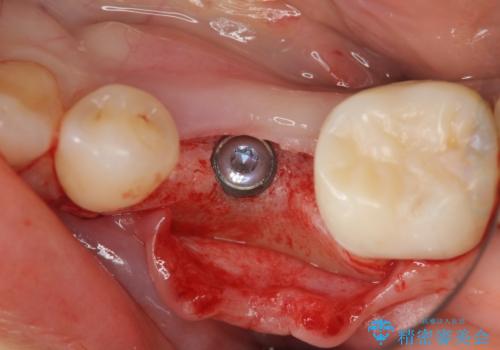

乳歯を抜去して歯ぐきの状態が落ち着いたのち、骨の増成を伴うインプラント治療を行い機能の回復を図ります。

残念ながらぐらつきが大きくなり、残すことが難しくなり抜去したのちインプラントを用いて咬合機能の回復をしっかりと行いました。